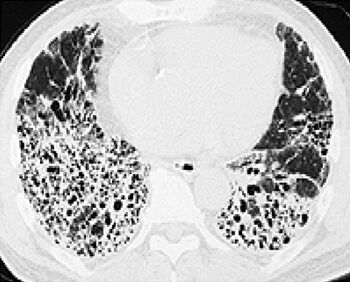

肺が繊維化してるから余命数年だろ

こんなだからな

肺真っ白になったというニュース流れてたし、後遺症が心配だな

60前で肺やられると社会生活かなり制限される

肺は大丈夫なんだろうか

治るのかこの肺

だめになった部分の肺は元には戻んないからな